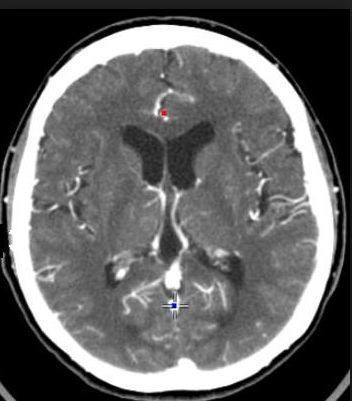

运用X线的原理,机器从一端发射射线经过人体,而机器的另一侧接收射线,并根据透射过来的射线多少来判断人体内部的情况。建立在此原理的基础上,CT就是一个发射射线、接收射线并且快速围着人转动的机器,以此来获得人体的内部图像。

CT图像主要反应的是人体内部的物理结构差异(组织强度越低,对射线的吸收(衰减)越低,成像图像显示为黑色,强度高则反之)。 CT图像显示的内容,只跟组织的强度有关,而与细胞的活性无关。